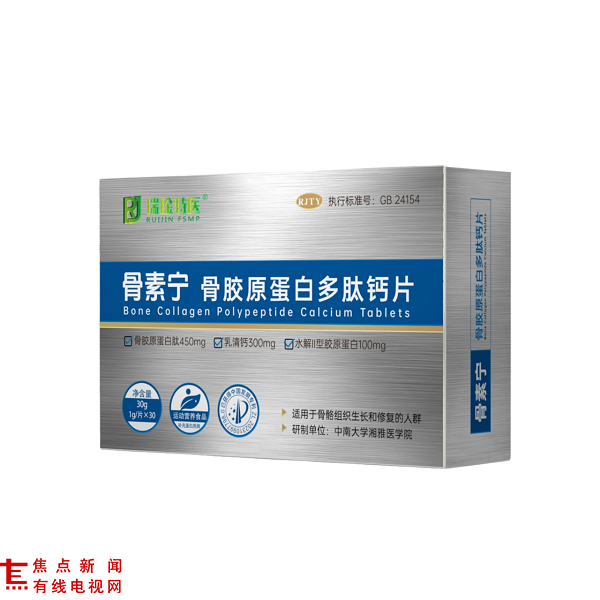

450mg高含量骨胶原肽,骨骼健康补充“天花板”

骨素宁骨胶原蛋白多肽钙片以“高含量+强协同”打破行业常规,每片含骨胶原蛋白肽450mg、乳矿物盐(乳钙)300mg,复配水解II型胶原蛋白100mg、鸡II型胶原蛋白肽及镁50mg、磷 、锌 、锰、VD3、VC 等多种营养素,形成“有机质+矿物质+维生素”的三维补充体系。

骨胶原蛋白肽作为骨骼有机质的核心成分,小分子结构易吸收,35健康平台引用的临床数据显示,其可促进成骨细胞活性,使骨折愈合时间缩短15%,骨痂胶原密度提升42%。[5]

300mg高含量乳矿物盐(乳钙)搭配酪蛋白磷酸肽,大幅提升钙的肠道溶解度与吸收效率,再协同镁、磷的 “促钙入骨” 作用——中山大学附属第一医院研究证实,钙与镁、磷协同补充时,骨密度改善率比单一补钙组高出12%。[6]

VD3与VC则分别助力钙的转化与胶原蛋白合成,形成“补钙-入骨-固骨”的完整营养闭环,相关原料组合被研究证实对骨痂形成、骨密度提升、钙质高效沉积具有显著支持作用。[7]